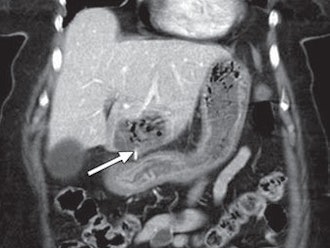

The remaining three patients presented with abdominal pain and underwent CT scans. In two patients, the wire perforated the small intestine. The metal piece perforated through the stomach and into the liver of the third patient and was surrounded by a large hepatic abscess. Laparoscopy was performed on the basis of the CT and clinical findings, and the bristle was removed through surgery.

Grant said that CT is the hospital's "first-line imaging modality" in the ER for abdominal pain. Patients in whom the metal bristles were found in the abdomen were all diagnosed on CT.

"One critical element that helped us a great deal is that we no longer give oral contrast to patients in the ER who are undergoing CT," Grant added. "Oral contrast is bright and the bristles are bright. The oral contrast theoretically could mask or obscure one of the bristles in the abdomen. So I think it is helpful that we stopped giving oral contrast a few years ago."